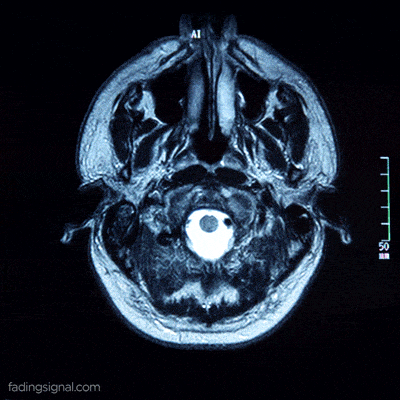

她刚刚度过了20岁生日,尽管在她原本应该充满沟回的大脑位置,只有一汪脑脊液和一小勺被称为“粉红色果冻”的残留组织。

据她父亲描述,她颅内仅存的实体,是位于后部的一小块小脑和脑干,大小仅相当于成人的小指。这残留的微小组织,即那勺“粉红色果冻”,在传统医学视角下通常被视为仅能维持心跳呼吸的生物残渣。然而事实诡异得令人不安,亚历克斯不仅活着,她还能感知。

而亚历克斯的情况截然不同,她是真正的“缺失”,她的神经元不是被压缩,而是被液化吸收殆尽。因此,亚历克斯的生存比那位法国公务员更具颠覆性,她证明了人类可以在没有皮层“硬件”的情况下,依然维持某种形式的“软件”运行。